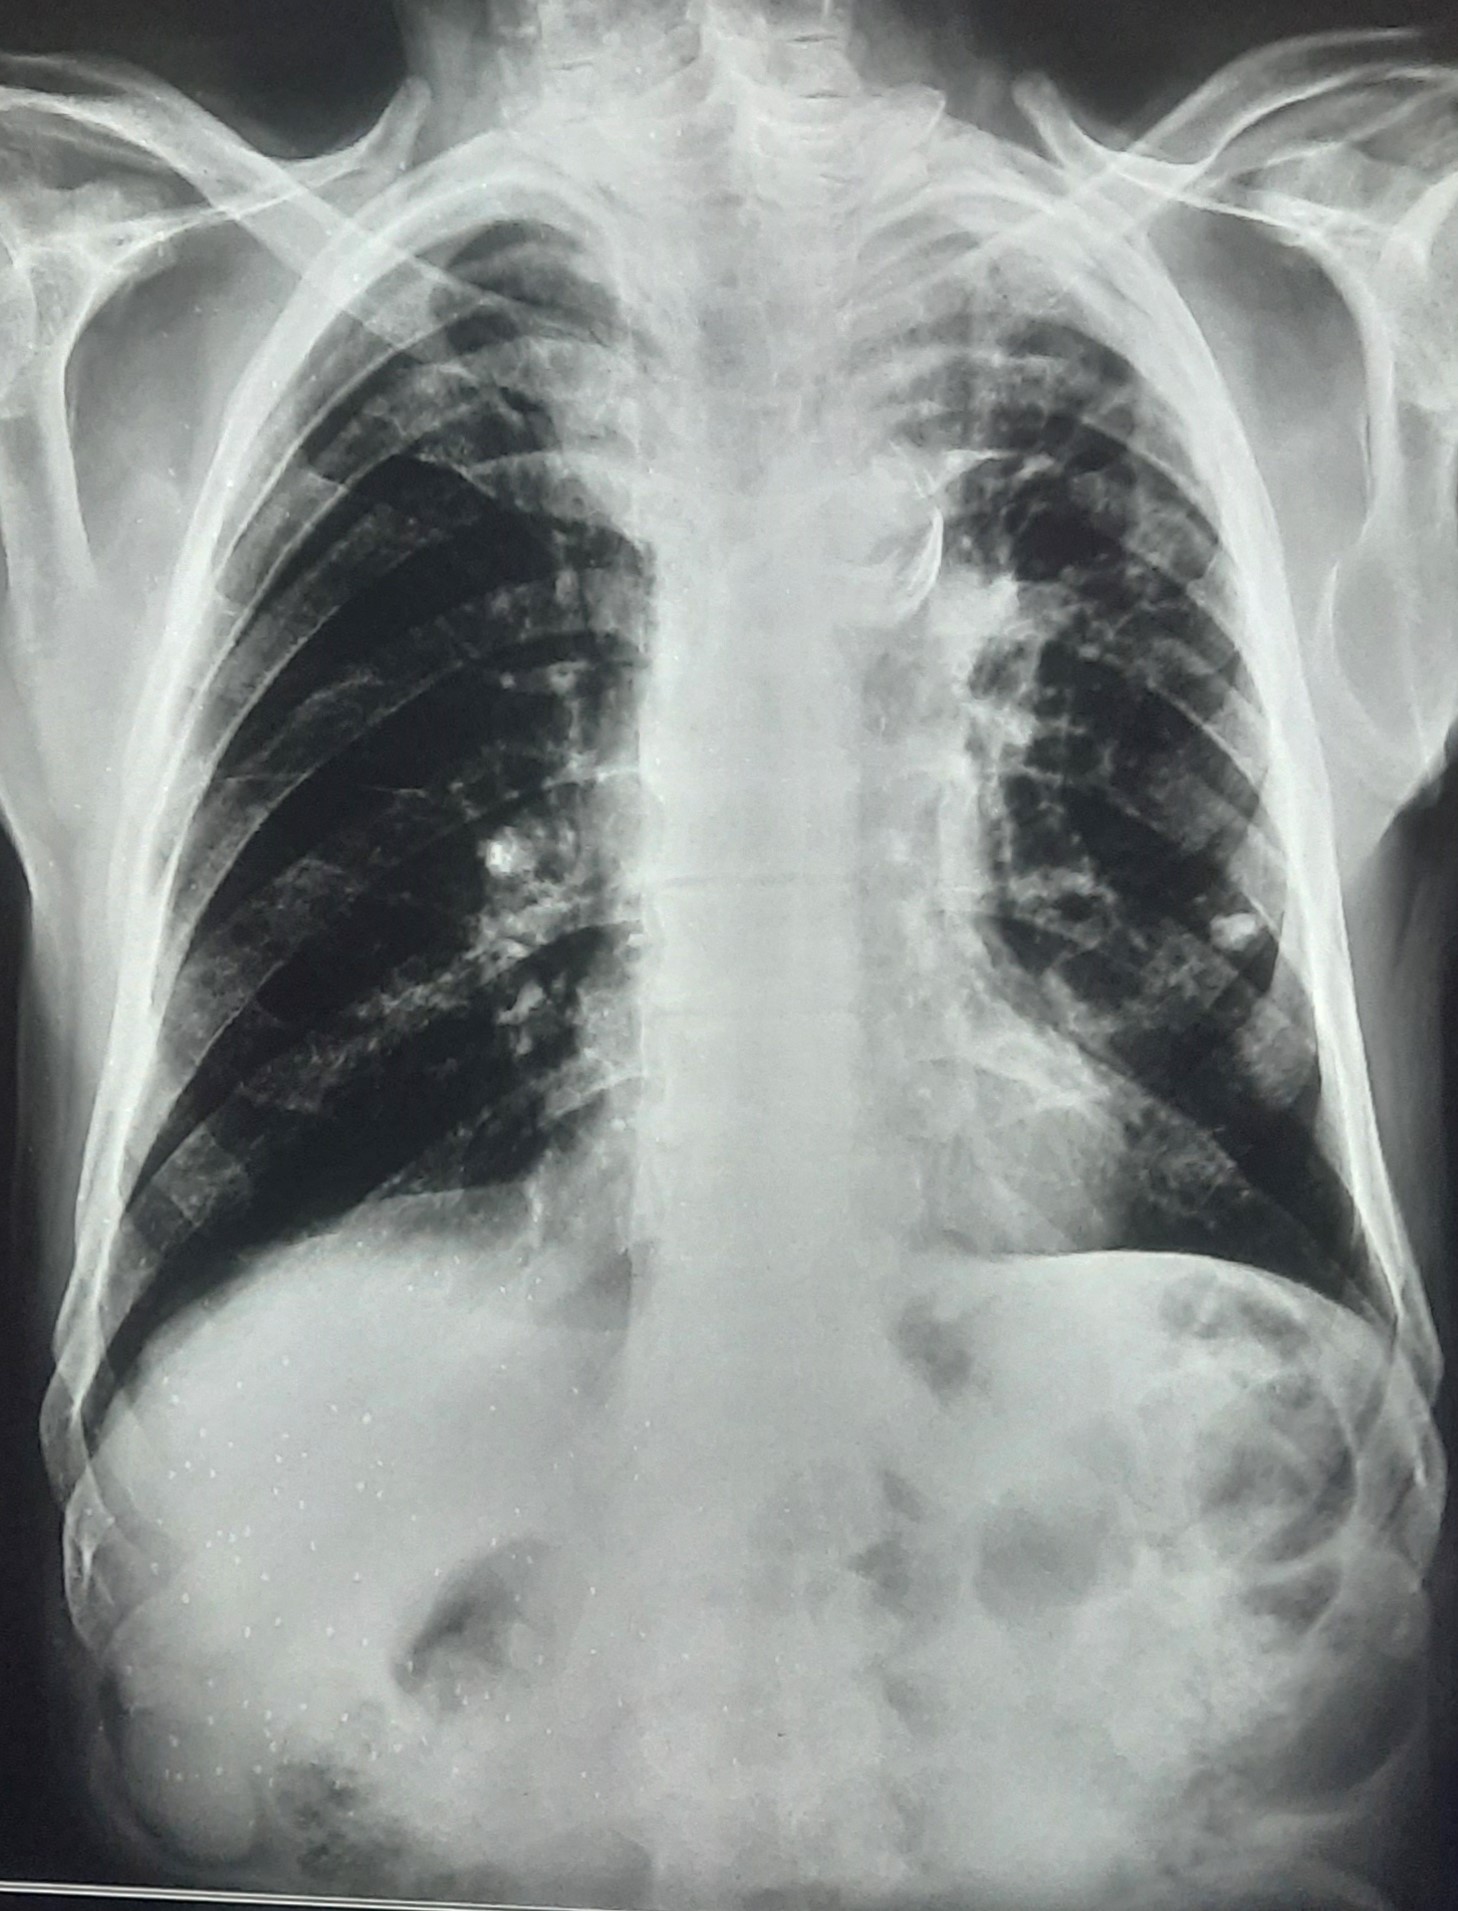

| 251 | IGGMC, Nagpur, Nagpur | P2 | 29-4221 | Ganpat Gaikawad | Consent taken on Paper | 70 Yrs. |

Provisional Diag : post TB sequele?

Final Diag : Fibrosis |

Non-TB Case (Confirmed) | Fibrosis | Abnormality visible on x-ray |